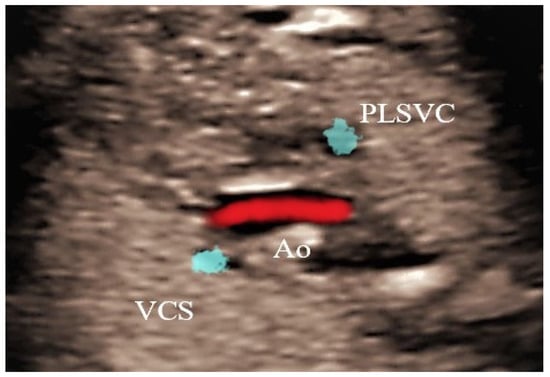

Persistent Left Superior Vena Cava Significance in Prenatal Diagnosis—Case Series

4. Cases—Ultrasound Findings Description